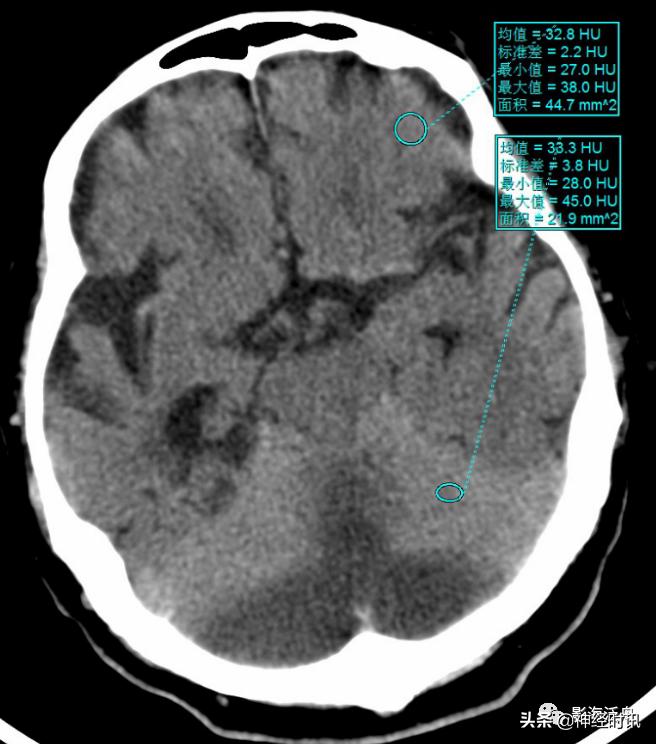

双侧小脑半球对称性脑梗死患者,小脑半球密度对称性减低,使得邻近的小脑幕呈相对高密度影,边缘模糊不清,类似于蛛血的影像表现。这种由于背景组织密度减低而导致正常组织密度异常“升高”的现象更常见于脂肪肝。尤其需要注意的是,发生大面积对称性脑梗时,不要把密度相对增高的大脑镰、小脑幕误诊为蛛网膜下腔出血。

测量上述患者正常脑组织和“密度增高的”小脑幕,可以发现两者CT值其实差不多,由于背景组织的干扰,你所看到的不一定就是真实的!